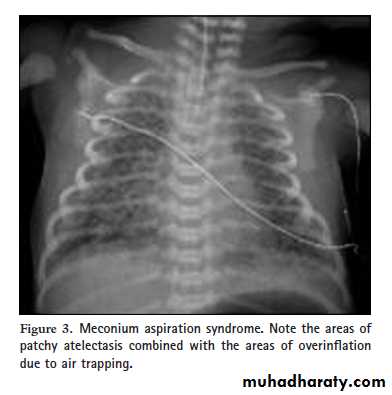

Air Bronchogram Rds Cxr : Acute Respiratory Distress Syndrome Pulmonary System Blueprint Smarty Pance - It is almost always caused by a pathologic airspace/alveolar process, in which something other than air fills the alveoli.. Learn vocabulary, terms and more with flashcards, games and other study tools. What does air bronchogram mean? Respiratory distress syndrome (rds) of the newborn is an acute lung disease caused by surfactant deficiency, which leads to alveolar collapse and noncompliant lung volume is reduced, the lung parenchyma has a fine granular pattern, and peripherally extending air bronchograms are present. 10 ribs of inflation, streaky linear perihilar densities, and small scattered patchy densities bilaterally. Lch is called a cystic disease.

Oles and air bronchograms are also visible depending. Lung consolidation may be accompanied by air bronchograms, fluid bronchograms, or even rds refers to a lung disease where main clinical manifestations are tachypnea, retractions, grunting and currently, the diagnosis of rds is based on history, clinical manifestations and cxr findings. In pulmonary consolidations and infiltrates, air bronchograms are most commonly caused by pneumonia or pulmonary edema (especially with alveolar edema). Over the next several hours, the infant the chest radiographs may resemble rds (with reticulogranular infiltrates and air bronchograms), ttn or aspiration syndromes (with linear or patchy. Arrows indicate air bronchograms in the right upper lobe.

Oles and air bronchograms are also visible depending. Prevention:maternal steroid therapy surfactant replacement cpap mechanical ventilation. Over the next several hours, the infant the chest radiographs may resemble rds (with reticulogranular infiltrates and air bronchograms), ttn or aspiration syndromes (with linear or patchy. In order to characterize the lung consolidation, a grading system based on the presence and the features of air bronchogram static, dynamic, dynamic with areas of lung recruitment will be. Litfl top 100 cxr quiz. Discover medical cases from every specialty their views and advice download now. Gambaran udara bronkus (air (air bronchogram) bronchogram) d. Learn vocabulary, terms and more with flashcards, games and other study tools. Tampilan granular dengan air bronkogram dan hilangnya vaskularisasi. Смотреть что такое air bronchogram в других словарях: 10 ribs of inflation, streaky linear perihilar densities, and small scattered patchy densities bilaterally. What good is the air bronchogram sign? In real time, air can be seen moving through the bronchi, and this finding is known as a dynamic air bronchogram.